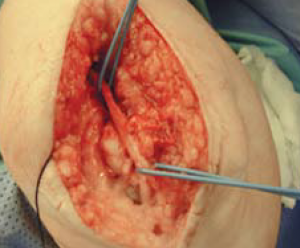

Hierbei wird in der von uns bevorzugten Technik nach Nirschl der krankhaft veränderte Anteil der Sehne des Musculus extensor carpi radialis brevis (ECRB) entfernt und der Knochen im Bereich des Epicondylus mehrfach angebohrt, so dass Blut heraustritt (Abb. 58). Durch die im Blut enthaltenen Zellen und Stoffe kommt es dann nach Naht der Sehnenansätze zu einer erneuten Heilung des Gewebes auf dem Epicondylus. Dieser Eingriff erfolgt in einer offenen Technik mit einem Hautschnitt von ca. 4 cm.